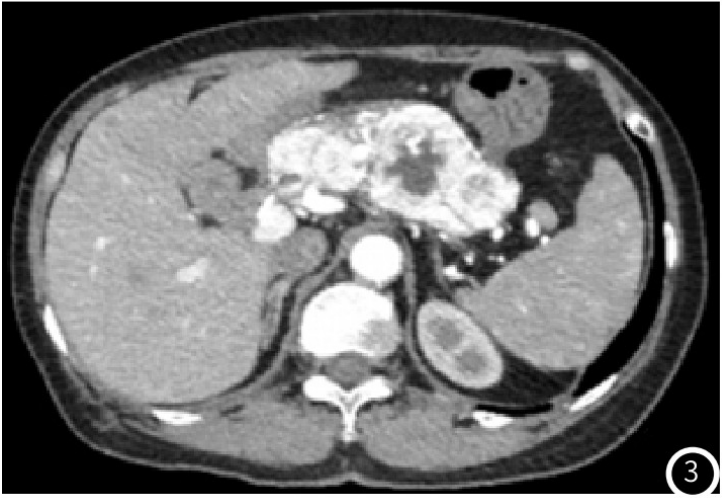

示胰头类圆形低密度结节,大小约14mm×12mm,增强扫描动脉期结节明显均匀强化(图1),强化程度高于正常胰腺实质,静脉期强化减低,边界清;术后4年常规胸腹部CT

图3 CT增强动脉期胰腺实质内多发不均匀明显强化肿块影,内见无强化的坏死区;